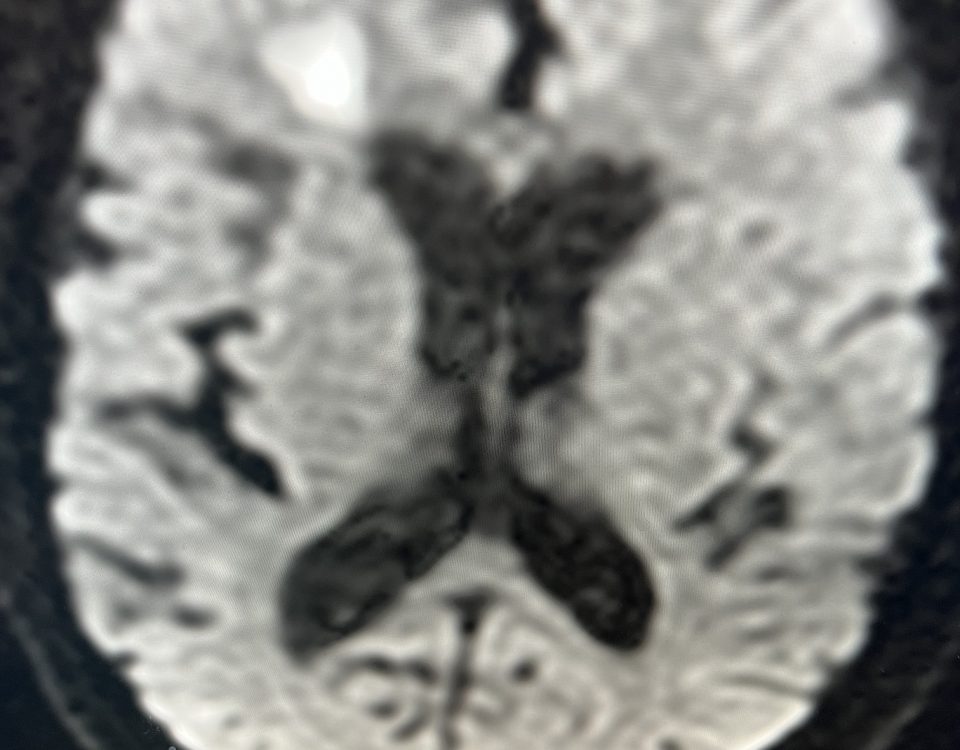

The patient is an 83-year-old man who has a history of hypertension and prior strokes who presented with a brief episode of left arm greater than […]